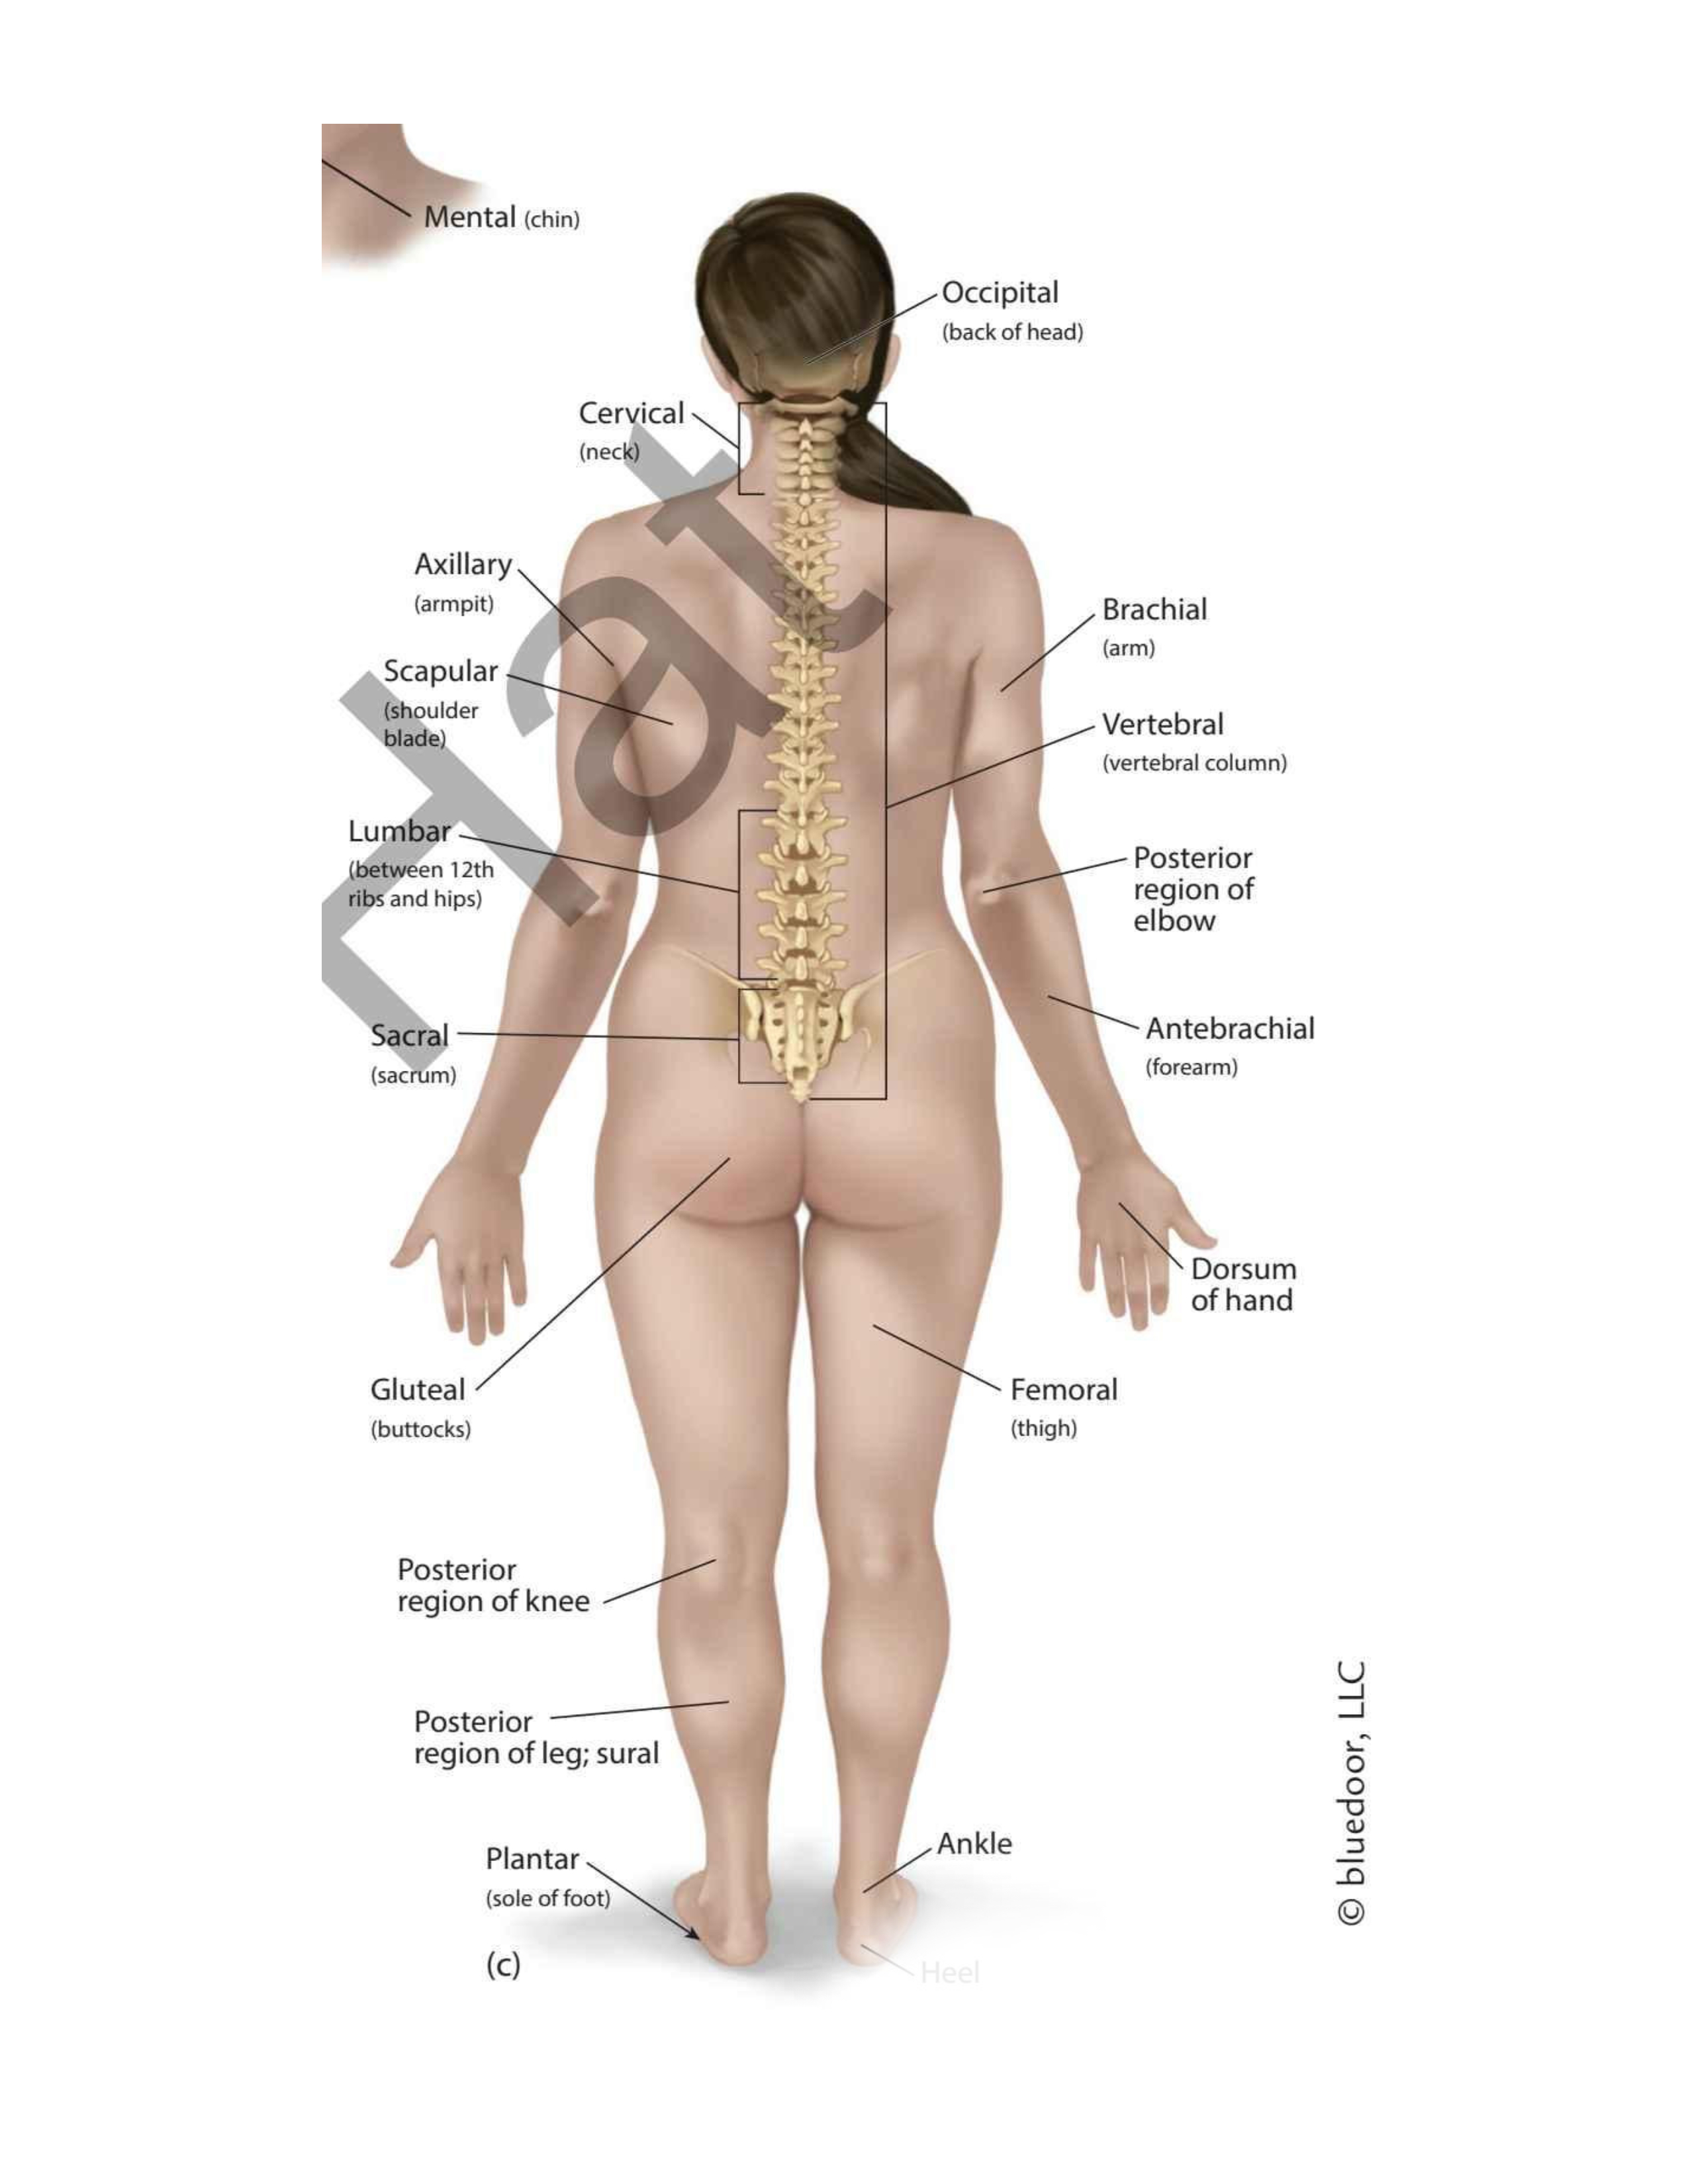

(forehead)

Frontal

(chin)

Mental

(wrist)

Carpal

(thigh)

Femoral

(elbow)

Antecubital

(back elbow)

Olecranal

(back knee)

Popliteal

(heel)

Calcaneal

(shoulder blades)

Scapular

(sole)

Plantar